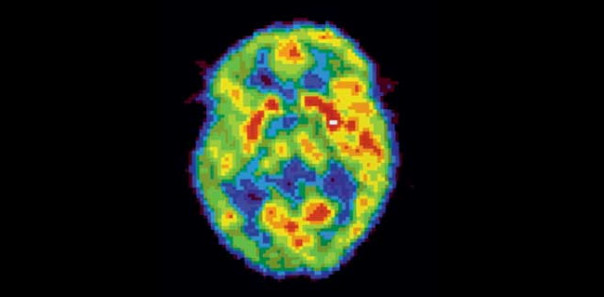

Активность мозга сильно различается не только во время бодрствования и сна — есть множество промежуточных состояний, которые можно различить во время позитронно-эмиссионной томографии.

НЕСПЯЩИЙ МОЗГ. Активность мозга в этой стадии (красные зоны на снимке) похожа на то, что происходит в REM-сне